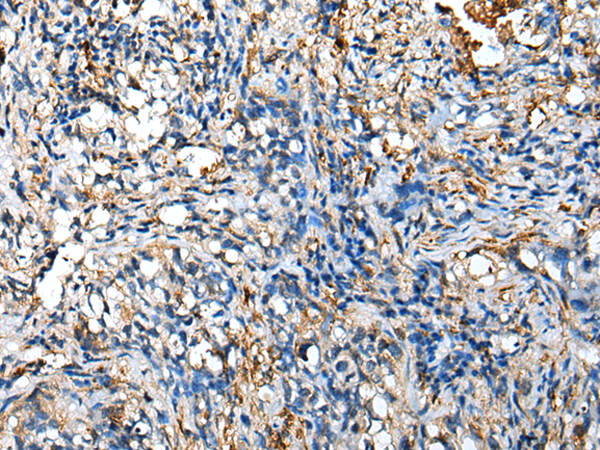

分类: 科研抗体货号: P02143别名: DIPP2; HDCMB47P; DIPP2beta; DIPP2alpha应用: IHC反应种属: Human, Mouse, Rat